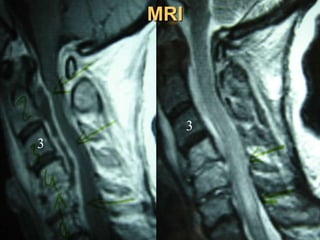

2nd case

Ma. Pal.

F 56 – Lawyer

Symptoms

 Neurologic deficit

 Cervical Pain

 Low fever

Laboratory

 Neutroph. ↑

 SR 50

56

X-rays

Unknown origin

MRI

3

Anterior procedure

Vertebrectomy - PUS evacuation + Stabilization

Posterior stabilization